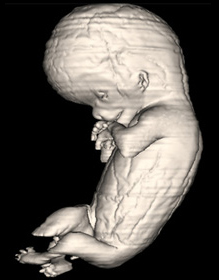

Carnegie Embryo #9226 | Location: 77-01-01

Source: The Virtual Human Embryo.